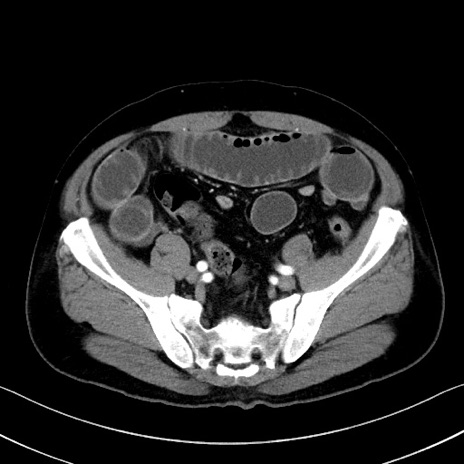

冠状断像

【症例】70歳代 男性

【主訴】腹部膨満、嘔吐

【現病歴】昨日より腹部膨満感出現。本日増悪し、仙痛出現。嘔吐あり、受診。

【既往歴】糖尿病、胆摘後

【身体所見】BP 149/80mmHg、HR 74/min、BT 35.9℃、腹部:膨満、軟、圧痛なし。腸雑音減弱あり。上腹部正中切開瘢痕あり。

【データ】WBC 13500、CRP 1.72